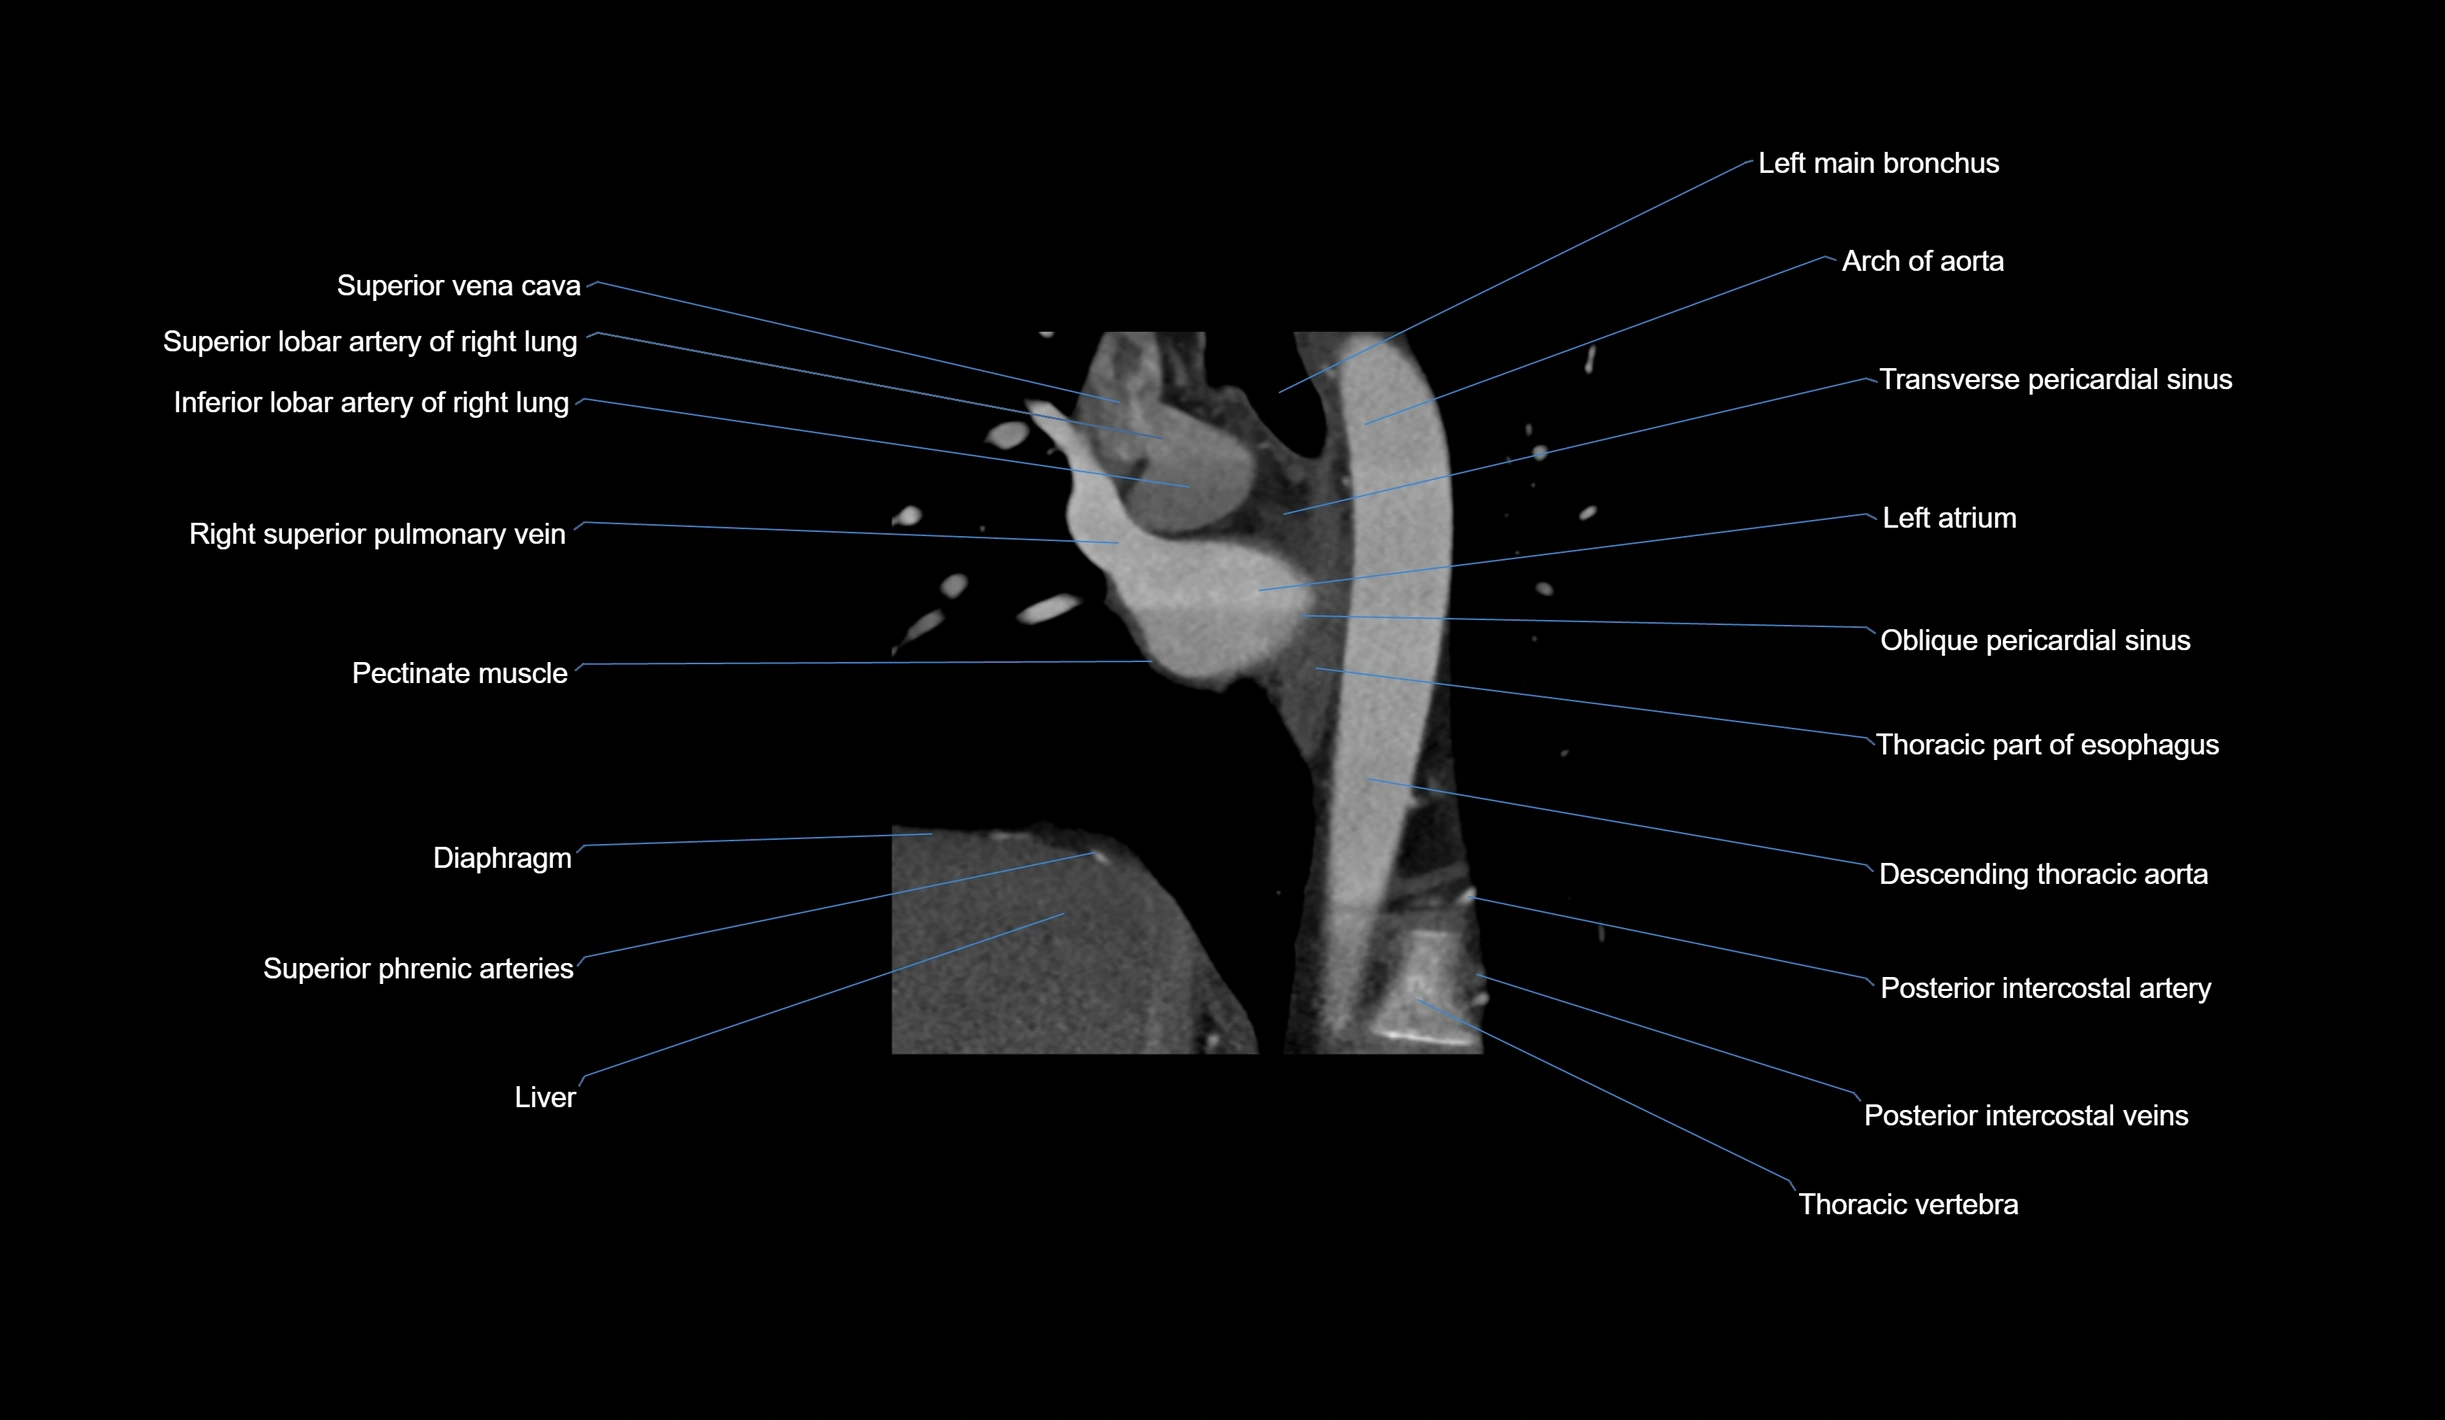

- Arch of aorta

- Left main bronchus

- Oblique pericardial sinus

- Left atrium

- Left auricle

- Superior vena cava

- Diaphragm

- Posterior intercostal arteries

- Posterior intercostal veins